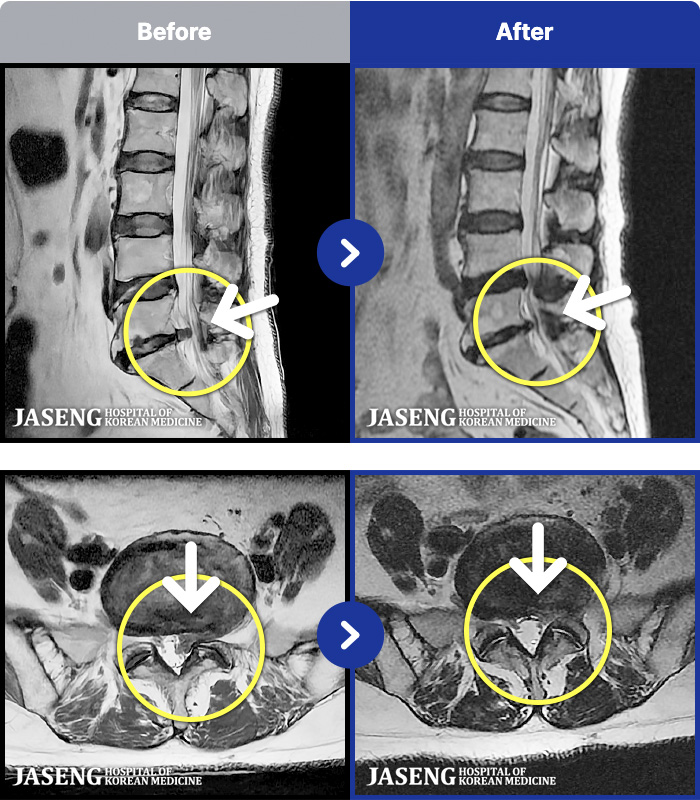

1,304 MRI ũ ʸ Ȯϼ.

[뱸] 19.11.28~25.05.06